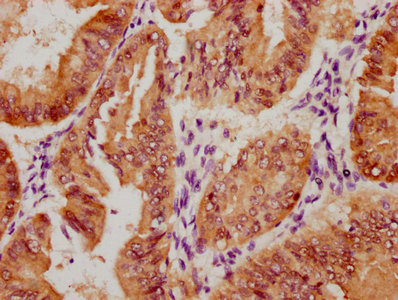

Immunohistochemistry of paraffin-embedded human testis tissue using CSB-PA525314HA01HU at dilution of 1:100